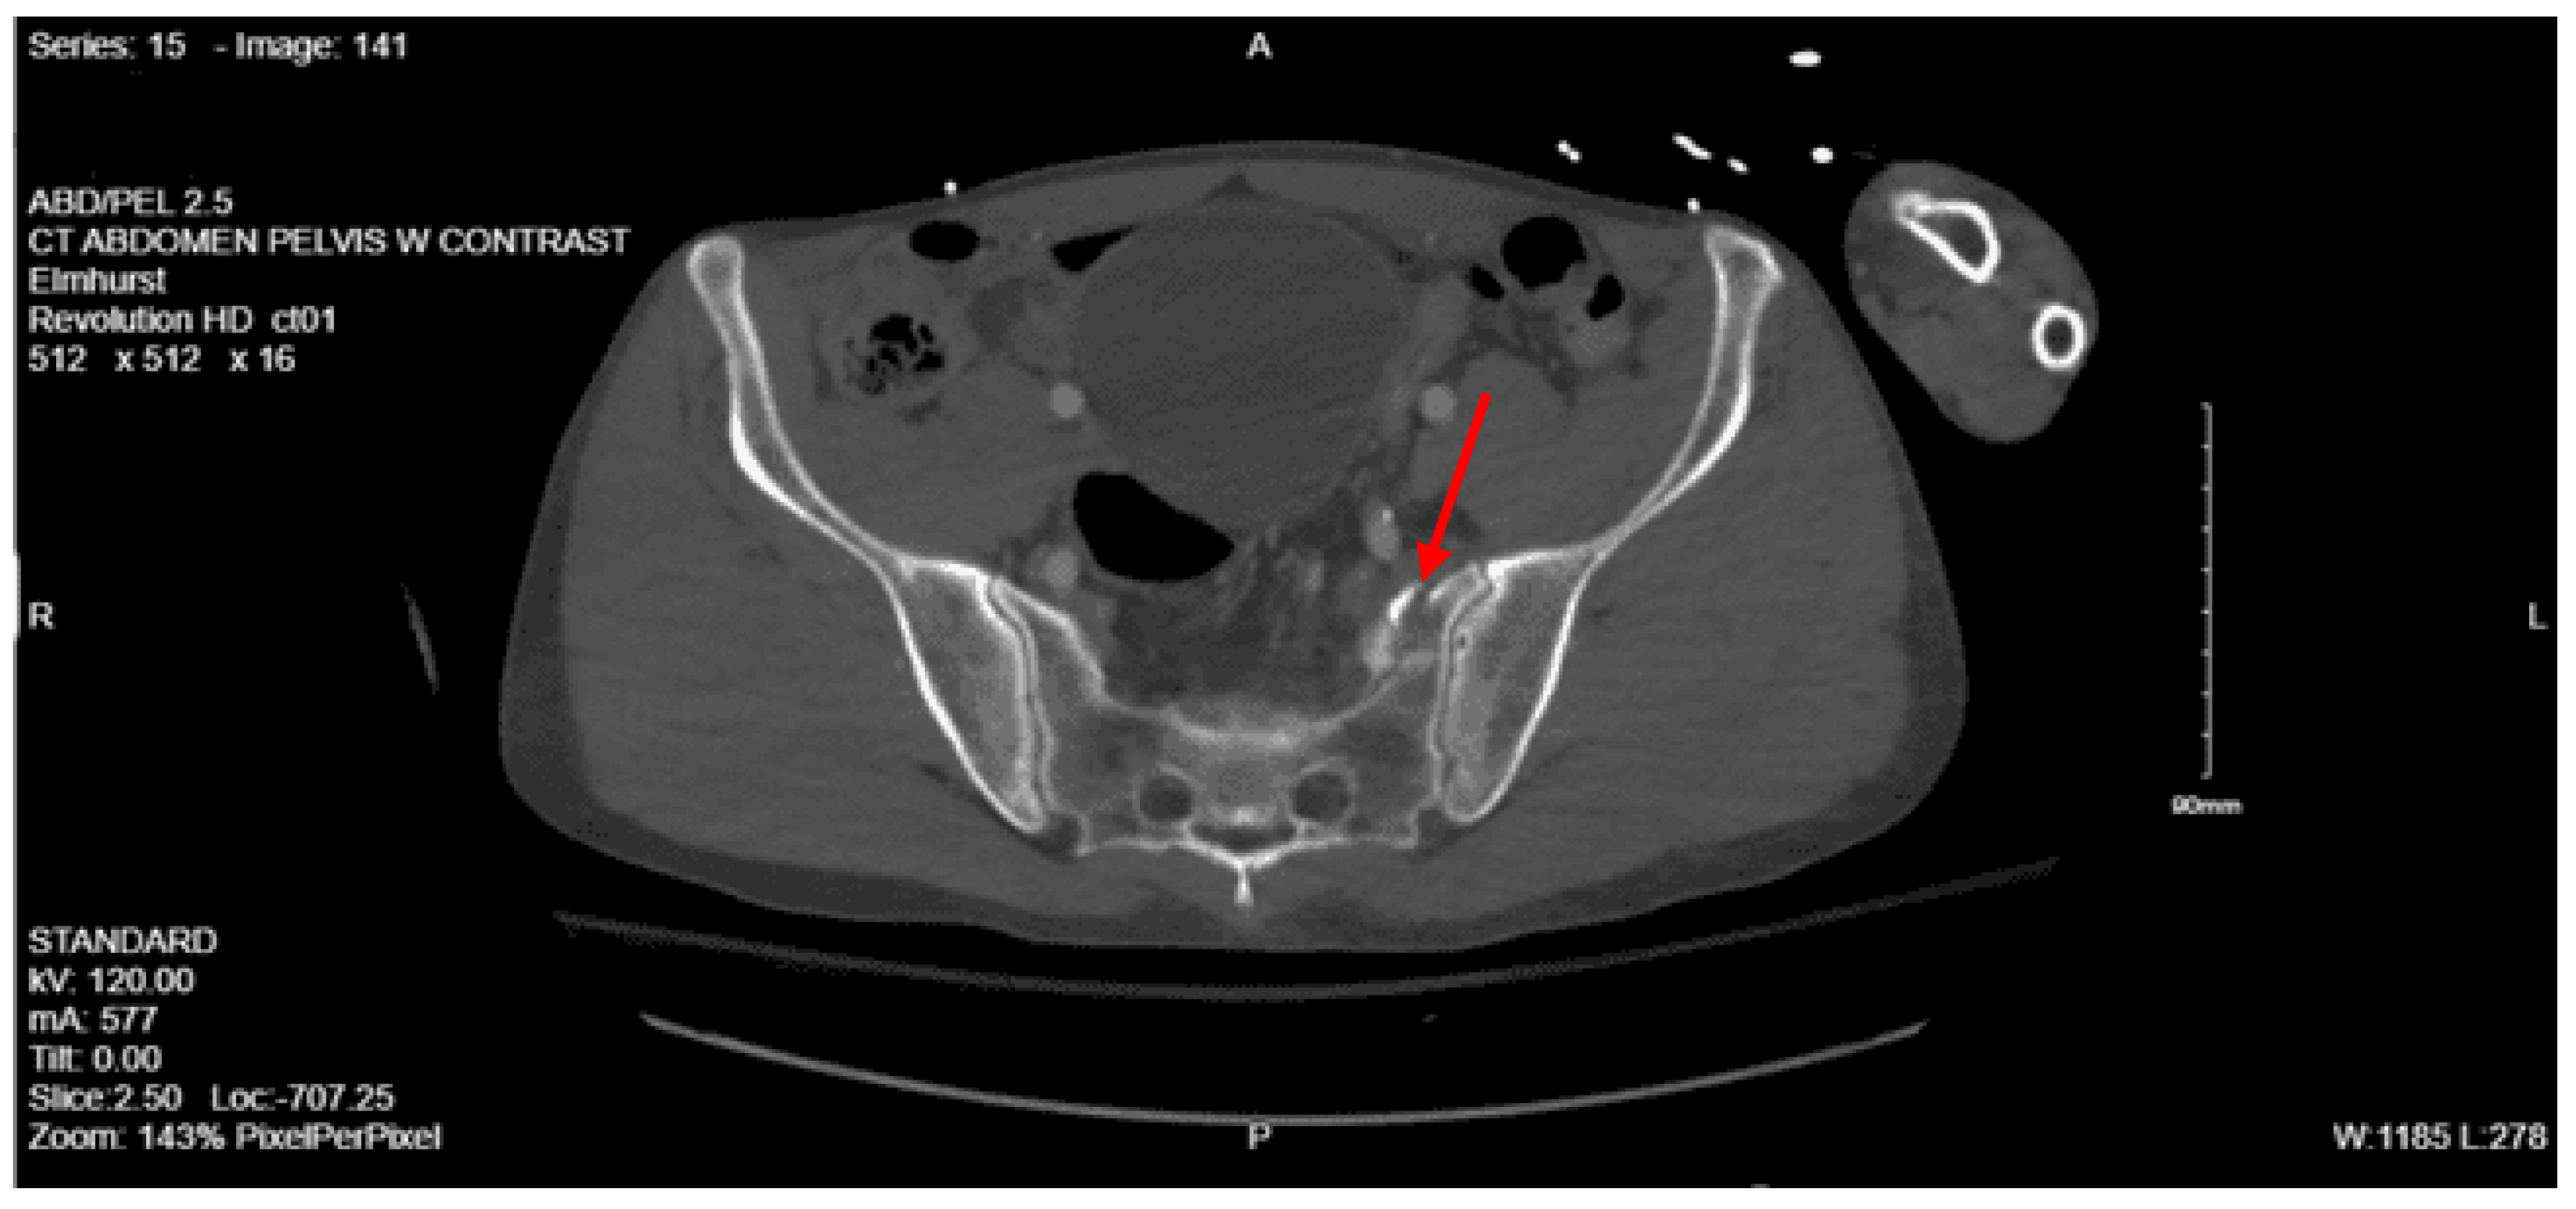

Imaging as shown in Figure 4, Figure 5 and Figure 6:

Portable pelvis x-ray: Acute impacted fracture involving the left superior pubic ramus in its medial aspect. Possible fracture, which is nondisplaced, involving the left inferior pubic ramus. The right superior and inferior pubic rami are intact. Femoral acetabular joints were unremarkable.

CT abdomen and pelvis with contrast: No acute visceral traumatic abnormality. There is evidence of an acute impacted fracture involving the left superior and inferior pubic rami. The right superior and inferior pubic rami are intact. The sacrum and coccyx appear unremarkable.

During her hospital course, the patient was also found to have a right lateral tibial plateau fracture and bilateral sacral ala fractures; orthopedic surgery recommended non-weight bearing for the RLE, and neurosurgery recommended bed rest. She required multiple blood transfusions due to repeated drops in hemoglobin/hematocrit but remained hemodynamically stable. Given her continued intubation status, tracheostomy was performed on hospital day 8. Continued monitoring via CT head with and without contrast continued to show evolving strokes and persistent severe vasospasm. On hospital day 13, the patient was seen by physical medicine and rehabilitation, who recommended physical and occupational therapy and TBI unit vs sub-acute rehab for discharge when the patient was medically stable. The patient’s mental status gradually started to improve, and she was transferred to the surgical stepdown unit on hospital day 15. On hospital day 19, PEG was placed by interventional radiology. The patient continued to slowly improve, and tracheostomy decannulation was performed on hospital day 36; then she was discharged to TBI rehab 3 days later.